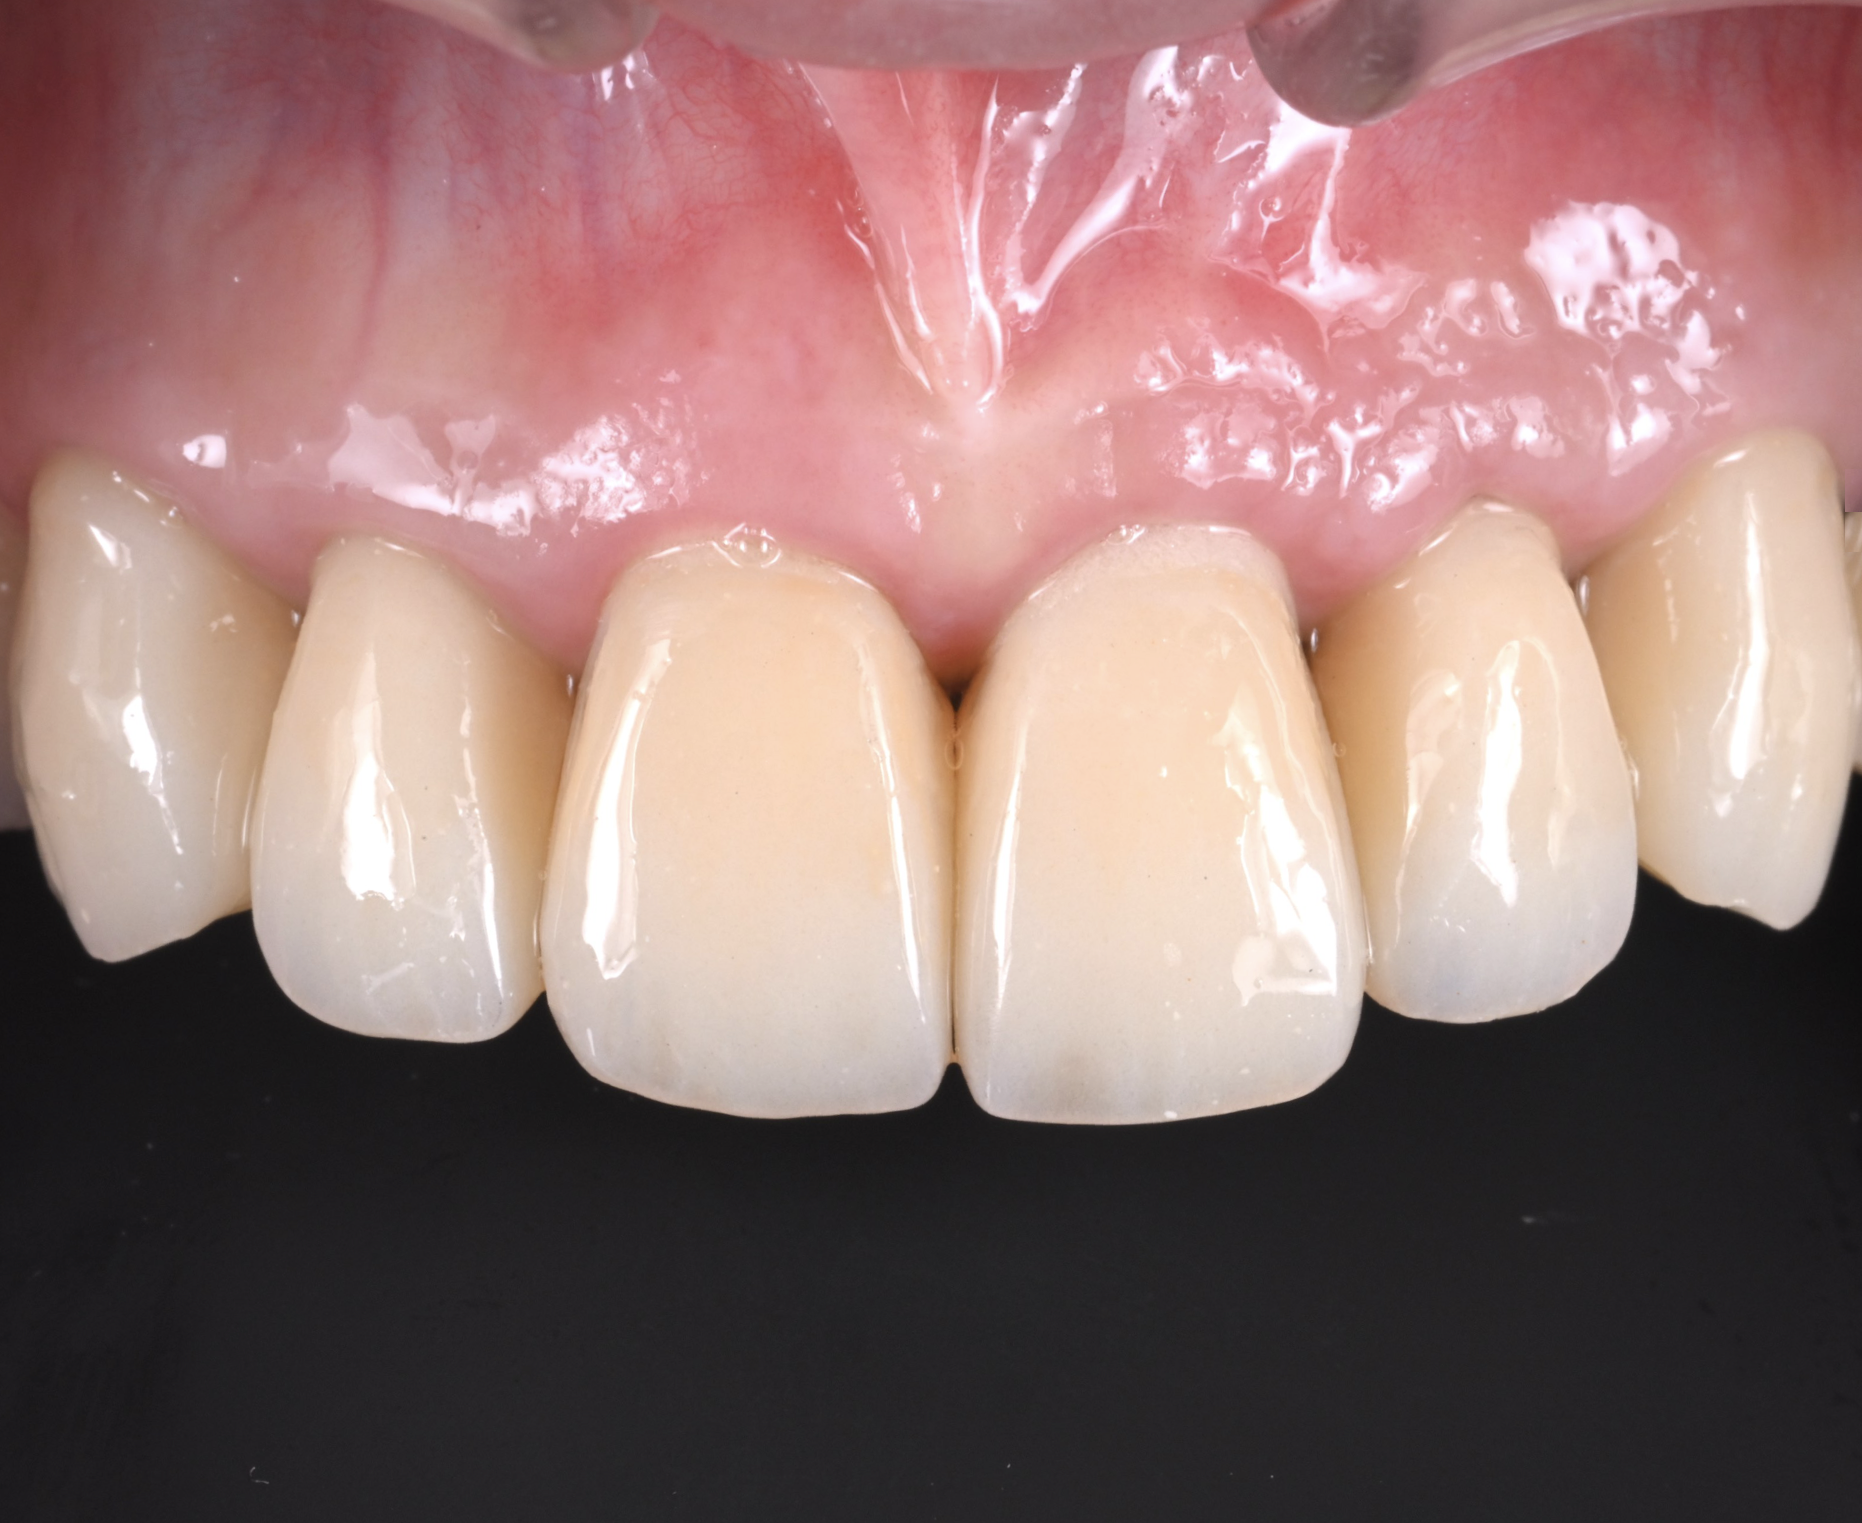

治療後

根管治療、そして骨補填剤を駆使して1年ほど。

喪失していた骨も再生し、見違える状態にまで回復しました。

口腔内写真